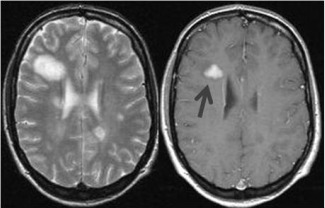

L'esclerosi múltiple afecta predominantment a dones joves, no es coneix el seu origen ni té tractament curatiu, però pot seguir-se el seu desenvolupament amb tècniques de diagnòstic per imatges, com la ressonància magnètica. El Dr. Rovira de la...